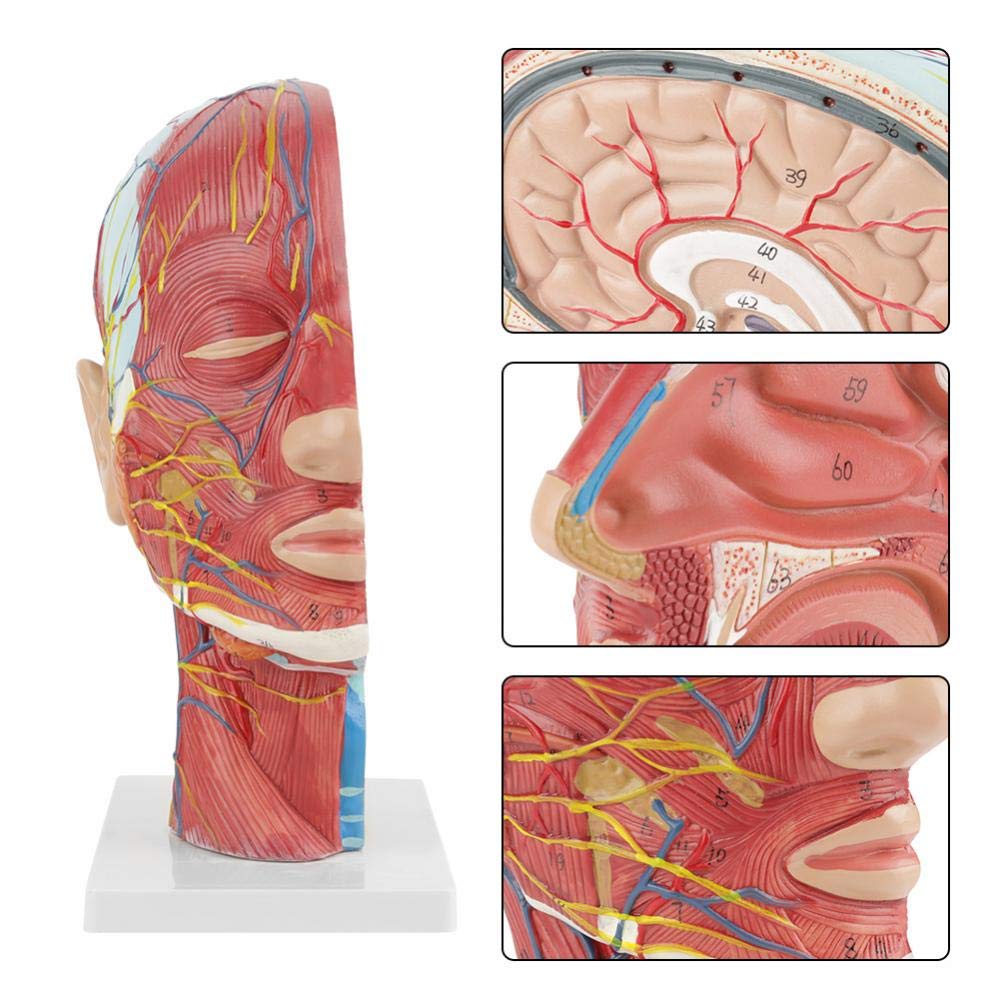

ਮਨੁੱਖੀ ਅੱਧਾ ਸਿਰ ਅਤੇ ਗਰਦਨ ਅਨਾਟਮੀ ਮਾਡਲ ਸਤਹੀ ਨਿ ur ਰੋਵਸਕੂਲਰ ਮਾਡਲ

ਮਨੁੱਖੀ ਅੱਧਾ ਸਿਰ ਅਤੇ ਗਰਦਨ ਅਨਾਟਮੀ ਮਾਡਲ ਸਤਹੀ ਨਿ ur ਰੋਵਸਕੂਲਰ ਮਾਡਲ

| ਉਤਪਾਦ ਦਾ ਨਾਮ | ਮਾਸਪੇਸ਼ੀ ਨਿ ur ਰੋਵਸਕੁਲਰ ਮਾਡਲ ਦੇ ਨਾਲ ਮਨੁੱਖੀ ਖੋਪੜੀ |

| ਸਮੱਗਰੀ | ਪੀਵੀਸੀ |

| ਮਾਪ | 21 * 12 * 27 ਸੈਮੀ |

| ਫੀਚਰ | ਮਾਡਲ ਸਿਰ ਅਤੇ ਗਰਦਨ ਦੇ ਅੰਦਰੂਨੀ ਅਤੇ ਬਾਹਰੀ ਪਾਸਿਆਂ ਦੇ ਅੰਦਰੂਨੀ ਰੂਪਨ ਵਿਗਿਆਨ ਦੇ ਨਾਲ-ਨਾਲ ਖੂਨ ਦੀਆਂ ਨਾੜੀਆਂ ਅਤੇ ਨਾੜਾਂ ਦੇ structures ਾਂਚਿਆਂ ਦਾ ਸਥਾਨਕ ਰੂਪ ਵਿਗਿਆਨ ਦਰਸਾਉਂਦਾ ਹੈ, ਅਤੇ ਇੱਥੇ 84 ਹਿੱਸੇ ਹਨ ਜੋ ਕੁੱਲ ਵਿੱਚ ਸੰਕੇਤ ਦਰਸਾਉਂਦੇ ਹਨ. |

【1: 1 ਦਾ 1 ਜੀਵਨ ਬਚਾਉਣ ਵਾਲਾ ਹਿੱਸਾ 1: 1 ਕੁਦਰਤੀ ਵੱਡੇ ਸਿਰ ਅਤੇ ਗਰਦਨ ਸਤਹੀ ਸੰਚਾਲਕ ਨਾਚਲਣ ਮਾਸਪੇਸ਼ੀ ਮਾਡਲ (ਸੱਜੇ ਪਾਸੇ). ਵਧੀਆ ਕਾਰੀਗਰ. ਐਨਾਟੋਮਿਕਲ ਵਿਸ਼ੇਸ਼ਤਾਵਾਂ ਦੀ ਪੂਰੀ ਸ਼੍ਰੇਣੀ ਦੀ ਪੇਸ਼ਕਸ਼.

【ਉੱਚ ਕੁਆਲਟੀ】 ਦਿਮਾਗ ਦੇ ਸਰੀਰ ਵਿਗਿਆਨਕ ਮਾਡਲ, ਗੈਰ-ਜ਼ਹਿਰੀਲੇ ਵਾਤਾਵਰਣ ਦੇ ਅਨੁਕੂਲ ਪੀਵੀਸੀ ਸਮੱਗਰੀ ਦਾ ਬਣਿਆ, ਸਾਫ ਕਰਨਾ ਅਸਾਨ ਹੈ. ਸਰੀਰ-ਚਿੱਤਰ ਨੂੰ ਹੱਥ ਨਾਲ ਪੇਂਟ ਕੀਤਾ ਜਾਂਦਾ ਹੈ ਅਤੇ ਵੇਰਵੇ ਵੱਲ ਪੂਰਾ ਧਿਆਨ ਨਾਲ ਇਕੱਠਾ ਕੀਤਾ ਜਾਂਦਾ ਹੈ.

【ਸਤਹੀ ਨਿ ur ਰੋਵਸਕੂਲਰ ਮਾਸਪੇਸ਼ੀ ਦਾ ਮਾਡਲ】 ਉੱਚਿਤ ਵਿਸਥਾਰਪੂਰਕ, ਨੰਬਰ ਮਾਰਕ ਕੀਤੇ, ਕੰਬਦੇ ਕੰ the ੇ, ਨਾੜੀ ਅਤੇ ਗਰਦਨ ਦੇ ਅੰਦਰੂਨੀ structures ਾਂਚਿਆਂ ਦੀ ਸਮਝ ਨੂੰ ਡੂੰਘਾ ਕਰੋ. ਲਾਲ-ਧਮਣੀ, ਨੀਲੀ-ਨਾੜੀ, ਪੀਲੇ-ਨਸ.

【ਵਿਸ਼ੇਸ਼ਤਾਵਾਂ】 ਦਾ ਸਾਹਮਣਾ ਕੀਤੇ ਚਿਹਰੇ ਦੀਆਂ ਸਤਹੀ ਮਾਸਪੇਸ਼ੀਆਂ ਨੂੰ ਦਰਸਾਉਂਦਾ ਹੈ; ਸਤਹੀ ਖੂਨ ਦੀਆਂ ਨਾੜੀਆਂ ਅਤੇ ਚਿਹਰੇ ਦੀਆਂ ਨਾੜੀਆਂ ਅਤੇ ਖੋਪੜੀ; ਪੈਟੀਡ ਗਲੈਂਡ ਅਤੇ ਵੱਡੇ ਸਾਹ ਦੀ ਨਾਲੀ ਦੇ ਅੰਦਰੂਨੀ structures ਾਂਚਿਆਂ; ਸਰਵਾਈਕਲ ਰੀੜ੍ਹ ਦੀ ਸੋਗਿਤਲ ਕਰਾਸ-ਸੈਕਸ਼ਨ structure ਾਂਚਾ.

】 ਐਪਲੀਕੇਸ਼ਨ】 ਇਹ ਮਾਡਲ ਡਾਕਟਰ ਦੇ ਦਫਤਰ, ਸਕੂਲ, ਹੋਸਿਟਲ ਅਤੇ ਕਲੀਨੈਕਸ ਲਈ ਪਹਿਲੀ ਪਸੰਦ ਹੈ. ਡਾਕਟਰ ਅਤੇ ਮਰੀਜ਼ਾਂ ਲਈ ਐਨਾਟਮੀ ਅਤੇ ਫਿਜ਼ੀਓਲੋਜੀ ਕੋਰਸਾਂ, ਪ੍ਰਦਰਸ਼ਨ ਸੰਦ ਲਈ ਸੱਚਮੁੱਚ ਇੱਕ ਵਧੀਆ ਅਧਿਆਪਨ ਸਹਾਇਤਾ.

ਇਹ ਮਾਡਲ ਮਨੁੱਖ ਦੇ ਸੱਜੇ ਸਿਰ ਅਤੇ ਮਨੁੱਖ ਦੇ ਮੱਧ ਸੇਂਟਟਲ ਭਾਗ ਦਾ ਵੇਰਵਾ ਦਰਸਾਉਂਦਾ ਹੈ. ਸਤਹੀ ਵੀ ਸ਼ਾਮਲ ਹੈ

ਖੁੱਲੇ ਚਿਹਰੇ ਦੇ ਮਾਸਪੇਸ਼ੀ; ਸਤਹੀ ਖੂਨ ਦੀਆਂ ਨਾੜੀਆਂ ਅਤੇ ਚਿਹਰੇ ਅਤੇ ਖੋਪੜੀ ਦੀਆਂ ਨਾੜੀਆਂ; ਅੰਦਰੂਨੀ structures ਾਂਚਿਆਂ

ਪੈਟੀਡ ਗਲੈਂਡ ਅਤੇ ਉਪਰਲੇ ਸਾਹ ਦੀ ਨਾਲੀ; ਸਰਵਾਈਕਲ ਰੀੜ੍ਹ ਦੀ ਸੋਗਿਤਲ ਕਰਾਸ-ਸੈਕਸ਼ਨ structure ਾਂਚਾ.

ਮਾਡਲ ਨੇ ਸਿਰ ਅਤੇ ਗਰਦਨ ਅਤੇ ਗਰਦਨ ਦੇ ਮੱਧਮ ਅਤੇ ਪਾਰਦਰਸ਼ੀ ਸਮੂਹਾਂ ਅਤੇ ਇਸ ਦੇ ਨਾੜੀ ਅਤੇ ਨਸਾਂ ਦੇ structures ਾਂਚਿਆਂ ਅਤੇ ਨਸਾਂ ਦੇ structures ਾਂਚਿਆਂ ਦਾ ਸਥਾਨਕ ਰੂਪ ਵਿਗਿਆਨ ਅਤੇ ਇਸ ਦੇ ਨਾੜੀ ਅਤੇ ਨਸਾਂ ਦੇ structures ਾਂਚਿਆਂ ਦਾ) ਕੁੱਲ 100 ਸਾਈਟ ਸੂਚਕਾਂ ਦੇ ਨਾਲ ਦਿਖਾਇਆ ਗਿਆ ਹੈ.

ਇਹ ਮਾਡਲ ਇੱਕ ਕੁਦਰਤੀ ਵੱਡਾ ਸਿਰ ਅਤੇ ਗਰਦਨ ਸਤਹੀ ਨਿ ur ਰੋਵਸਕੁਲਰ ਮਾਸਪੇਸ਼ੀ ਮਾਡਲ, 1 ਕੰਪੋਨੈਂਟ, ਚਿਹਰੇ ਅਤੇ ਖੋਪੜੀਆਂ ਦੇ ਸਤਹੀ ਮਾਸਪੇਸ਼ੀਆਂ ਦੇ ਵੇਰਵੇ ਦਿਖਾਉਂਦੇ ਹੋਏ, ਨਸਾਂ ਅਤੇ ਪੈਰੋਟਿਡ ਗਲੈਂਡ ਅਤੇ ਵੱਡੇ ਸਾਹ ਦੀ ਨਾਲੀ ਦਾ ਮੈਡੀਅਲ ਬਣਤਰ, ਅਤੇ ਸਰਵਾਈਕਲ ਰੀੜ੍ਹ ਦੀ ਸੋਗਟਲ ਸੈਕਸ਼ਨ ਦਾ structure ਾਂਚਾ